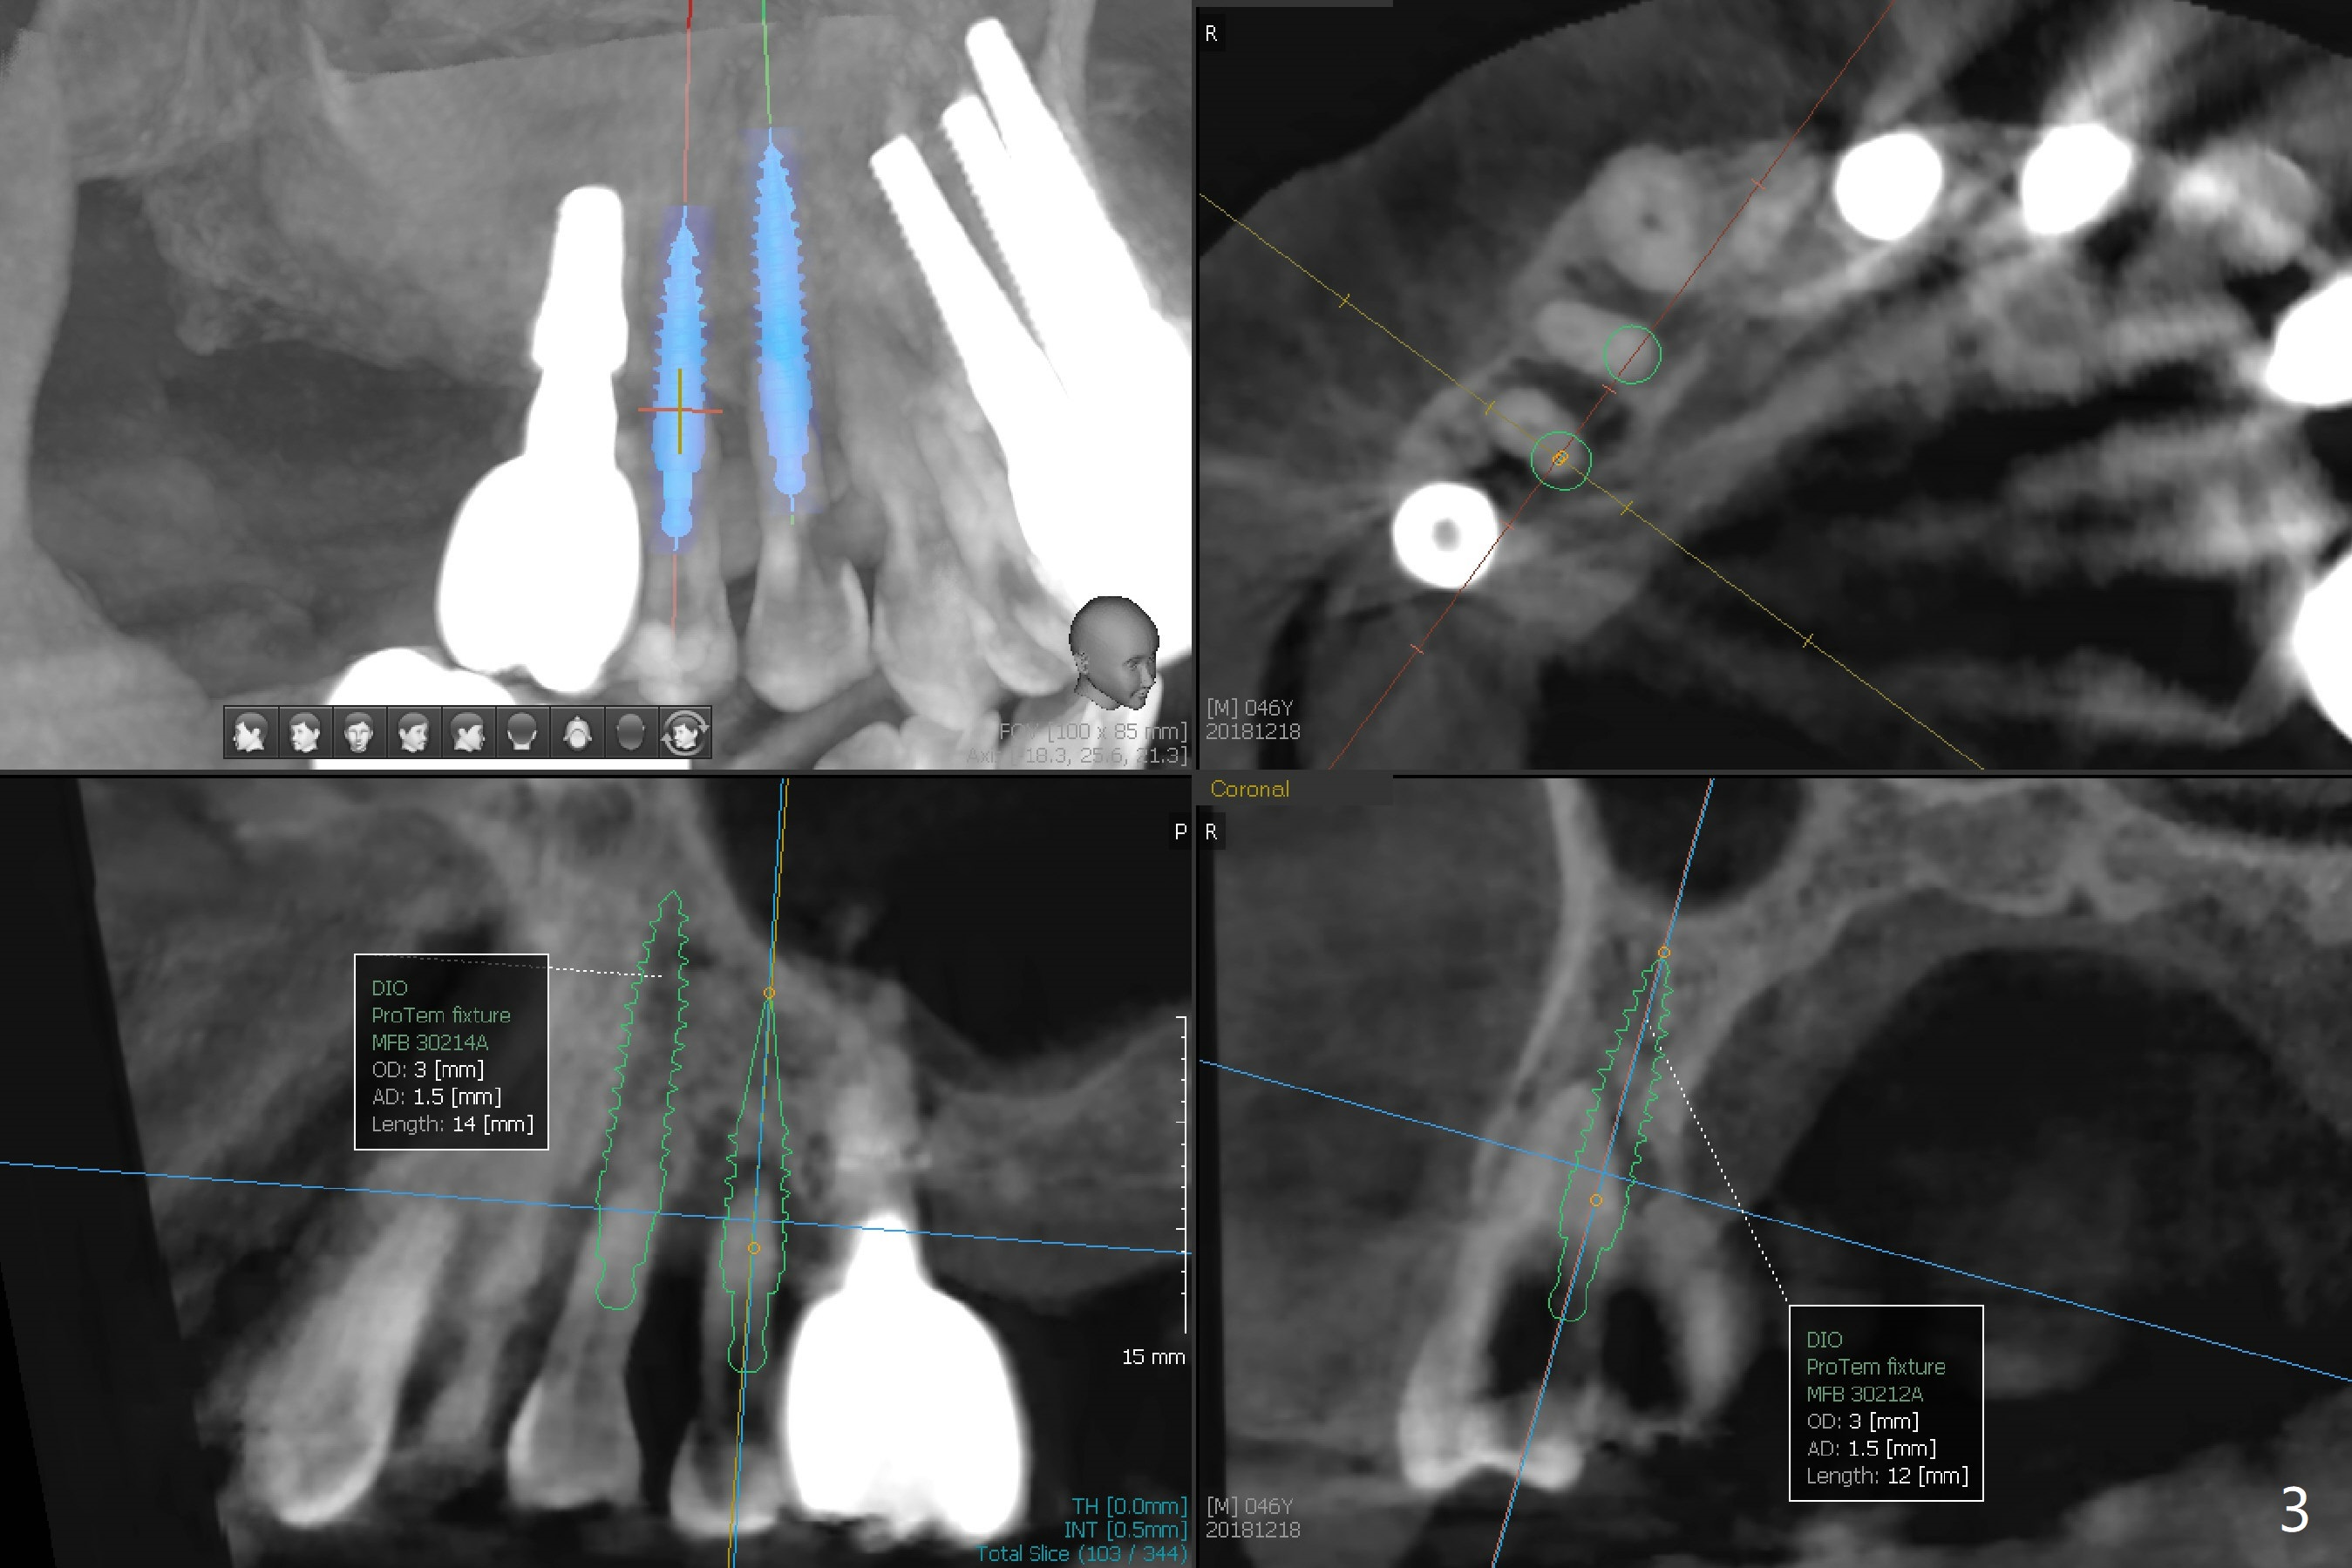

A 46-year-old man requests immediate implants at #4 and 5 because of pain associated with advanced periodontitis. Implants at #15 and 29 were removed with bone graft 4 months earlier (Fig.1). All of the 4 implants will be placed with guide. When 3.5 mm implants are placed at #4 and 5, they appear to be too close to each other (Fig.2). It is alright when the diameter changes to 3.0 mm (Fig.3). While a 5x10 mm implant will be placed at the 2nd stage (Fig.4), a 4x11.5 mm one will be placed in the same appointment as #4 and 5 (Fig.5).